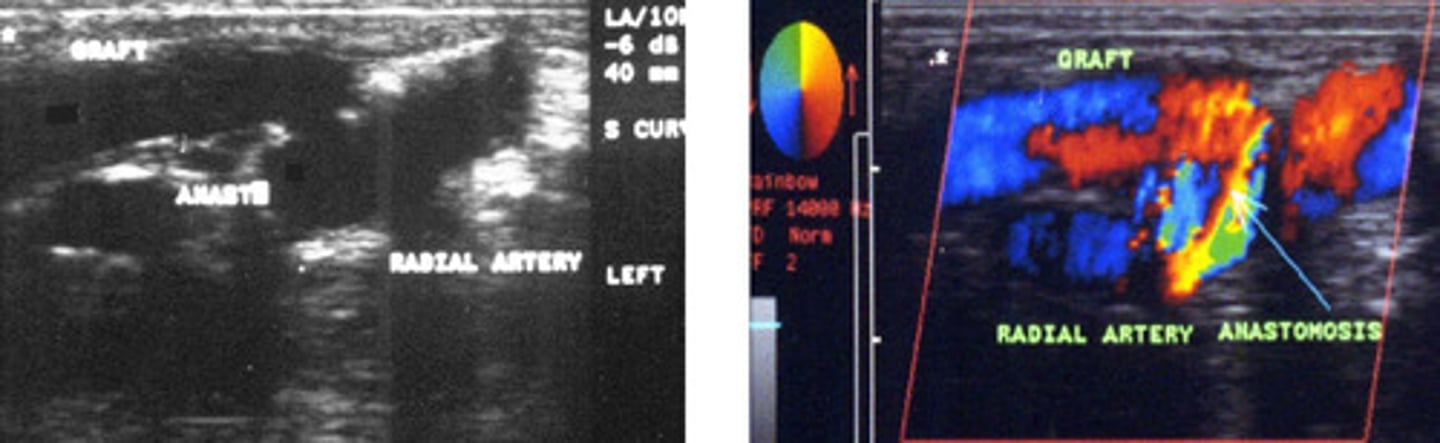

Graft

What does this image show

Radial artery to cephalic vein straight graft-> showing colour bruit so normal